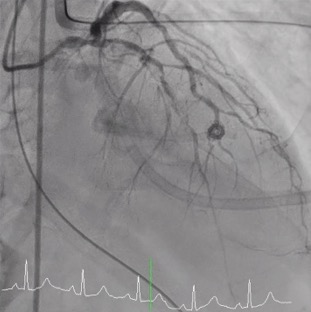

Procedural Step

Percutaneous coronary intervention (PCI) was initiated by a right femoral approach using a 7 Fr EBU 3.5 guide catheter. We started from NC balloon and cutting balloon for lesion preparation, then first BMS was deployed successfully but the 3.5 X 48mm DES was hard to push even by side branch and distal anchor technique. We changed our strategy from 1 long stent to 2 shorter stent with a shorter DES and it work. But, due to the jailed LCX orifice, the reversed culotte technique was used with the opened 48mm DES at the beginning as bail out 2 stent strategy. We were able to deployed the opened 48mm DES at the LM-LCX successfully, however, the balloon could not be deflated and was stuck! We hurriedly tried the opened cutting balloon and back-and-forth traction but failed. Even worse, the balloon shaft snapped! We tried to engage the guiding to catch the balloon but failed again. Overall, this was a catastrophe with an un-deflated fractured balloon trapped and stuck at the left main coronary artery.The patient complained of severe chest pain accompanied by a dropping blood pressure. We administered Bosmin with Levophed pump for the shock status and contacted the Cardiovascular surgeon and ECMO team immediately. For our last resort, we tried the Snare to catch the proximal tip of the undeflated fractured balloon and finally we succeeded. We were able to capture the balloon and retrieve it, with the angiography resulted expanded stent with normal coronary flow.